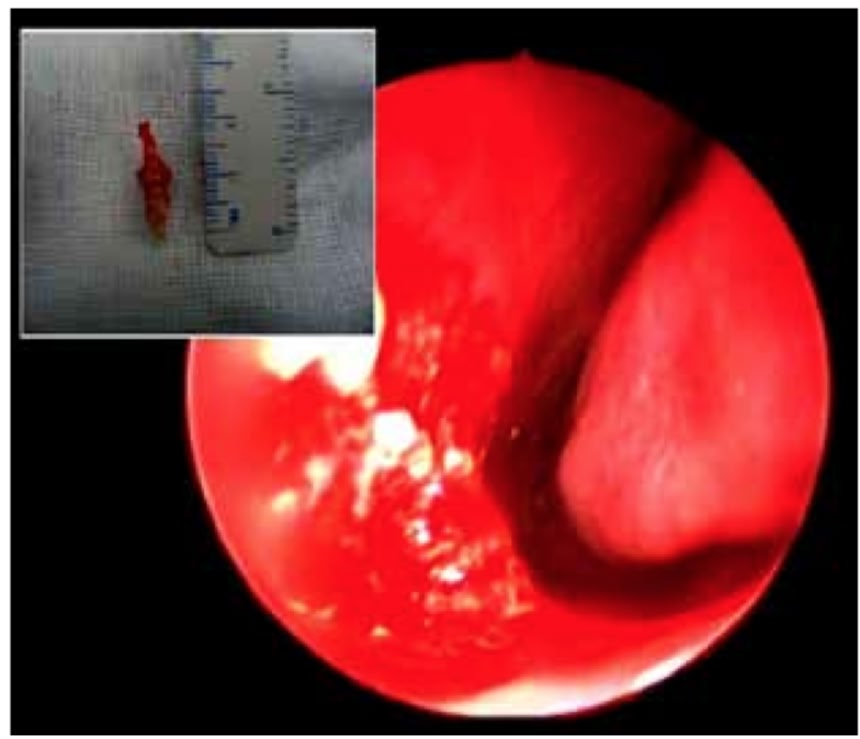

患者はその後全身麻酔での摘出手術にかけられ、術後は鼻血も止まり完治したようだ。この患者のケースは「アメリカン・ジャーナル・オブ・ケース・レポート」に掲載された。

この驚きのエピソードを持つ人は22歳のサウジアラビアの男性で、一ヶ月の間に1~2回起こる鼻血に3年もの間苦しめられていた。医者が患者の診察で発見したのは、約1センチの象牙色をした骨状の物だった。

この画像を大きなサイズで見る医師は歯科医の同僚と意見を交え、結果的に骨の正体は「余分に生えてきた歯だと思われる」と結論づけた。ちなみに患者の口内に存在する歯は完全に生え揃っており、本数も揃っていたそうだ。